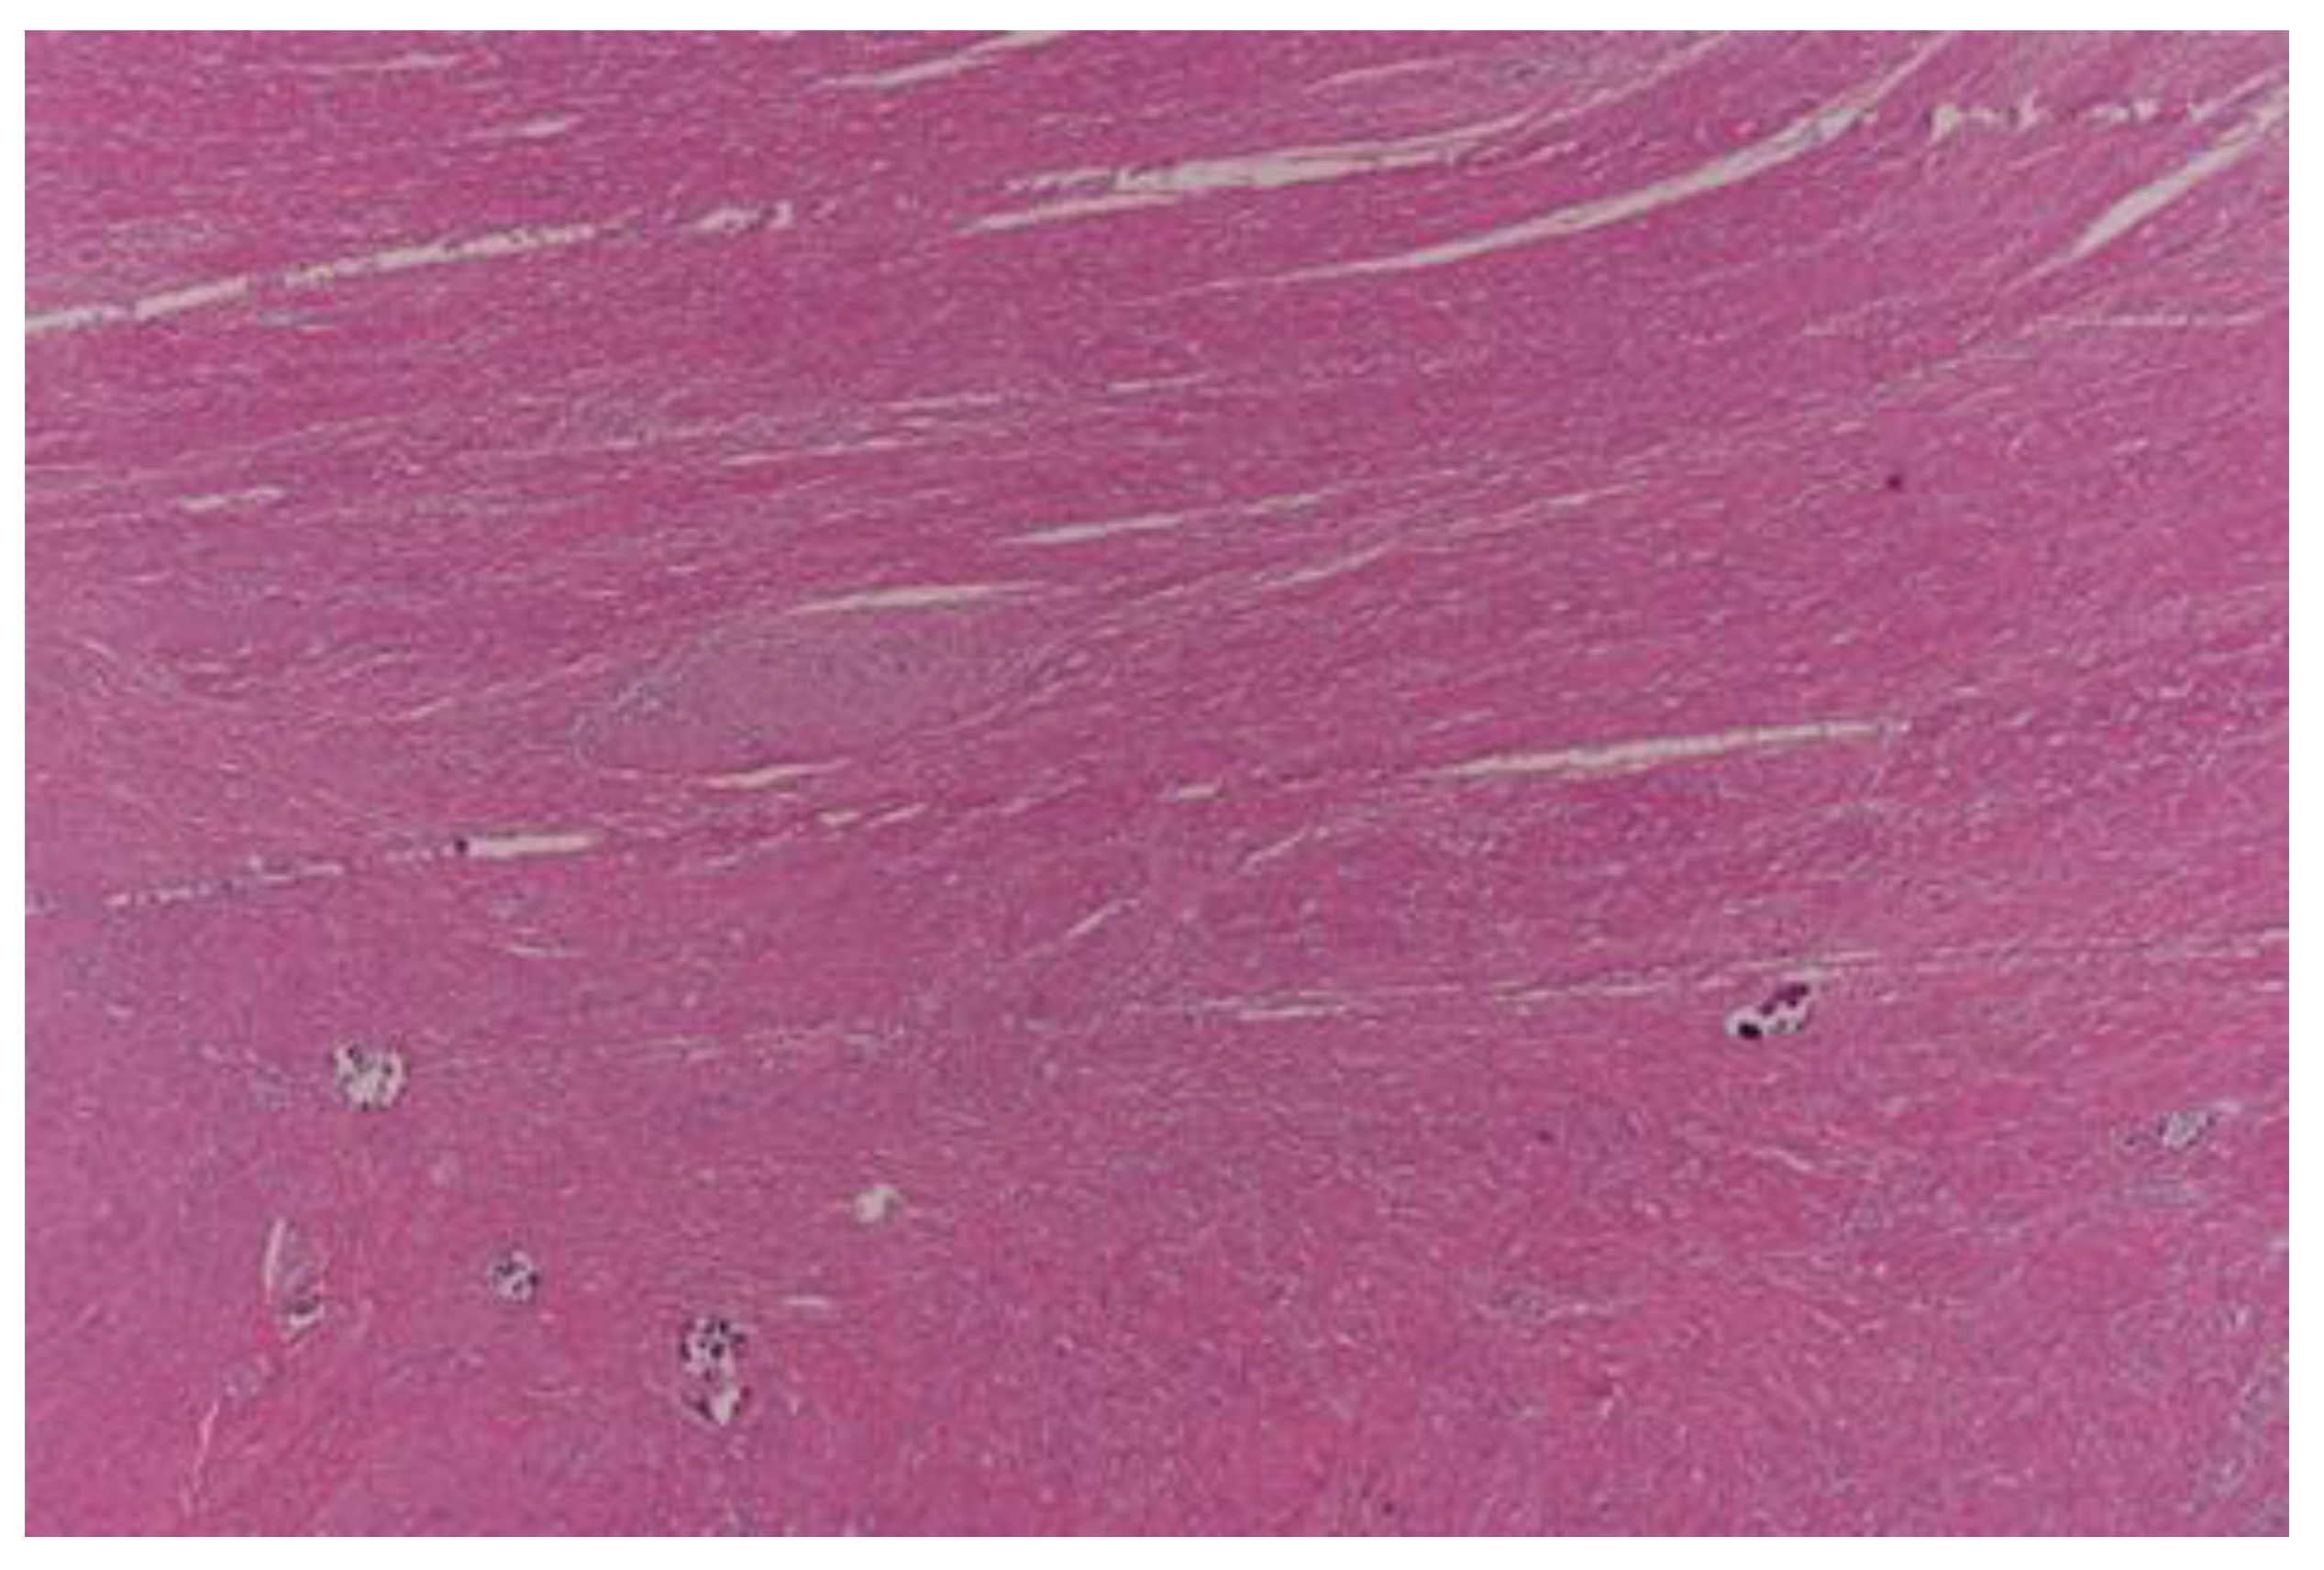

- Dworak, O.; Keilholz, L.; Hoffmann, A. Pathological features of rectal cancer after preoperative radiochemotherapy. Int. J. Color. Dis. 1997, 12, 19–23. [Google Scholar] [CrossRef] [PubMed]

- Ryan, R.; Gibbons, D.; Hyland, J.M.; Treanor, D.; White, A.; Mulcahy, H.E.; O’Donoghue, D.P.; Moriarty, M.; Fennelly, D.; Sheahan, K. Pathological response following long-course neoadjuvant chemoradiotherapy for locally advanced rectal cancer. Histopathology 2005, 47, 141–146. [Google Scholar] [CrossRef]

- Chen, H.Y.; Feng, L.L.; Li, M.; Ju, H.Q.; Ding, Y.; Lan, M.; Song, S.M.; Han, W.D.; Yu, L.; Wei, M.B.; et al. College of American Pathologists Tumor Regression Grading System for Long-Term Outcome in Patients with Locally Advanced Rectal Cancer. Oncologist 2021, 26, e780–e793. [Google Scholar] [CrossRef] [PubMed]